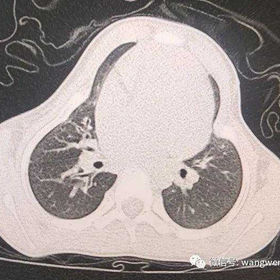

The patient’s thoracic cage is generally constricted, with a chest circumference of only 44.5 cm. The center of her anterior chest wall protrudes while the sides are concave. The patient was diagnosed with asphyxiating thoracic dystrophy.

The Wang procedure was performed to correct the depressions on both sides of the chest wall. The surgery lasted 2 hours and was completed successfully. After the surgery,the overall size of the patient's thoracic cage increased significantly, and the deformity was effectively corrected, yielding satisfactory results.